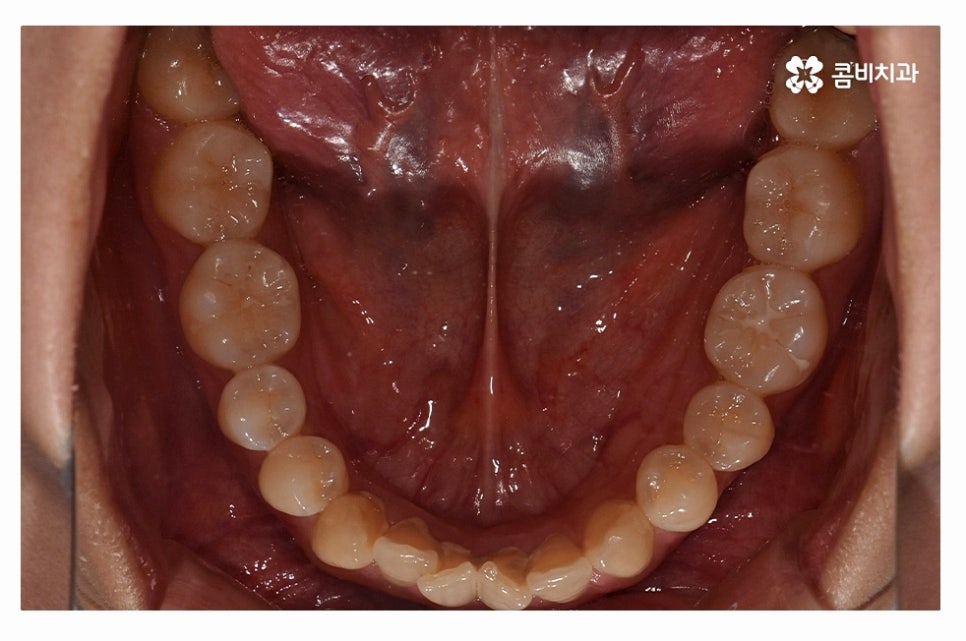

오늘 보여드릴 사례도 덧니교정이 비발치로 진행이 된 사례이며

치아의 이동 공간과 치아 상태, 골격, 얼굴형 등을

종합적으로 판단할 때 비발치로도 진행이 가능했던 사례라고 할 수 있어요.

덧니를 개선하려면 환자분들에 따라 골격부터 치아 구조 등을

정확히 파악해야 하며 치열이 이동하면서 바뀌게 되는 교합이나

얼굴 변화에 대해서도 종합적으로 예측하고 치료할 필요가 있는데요.